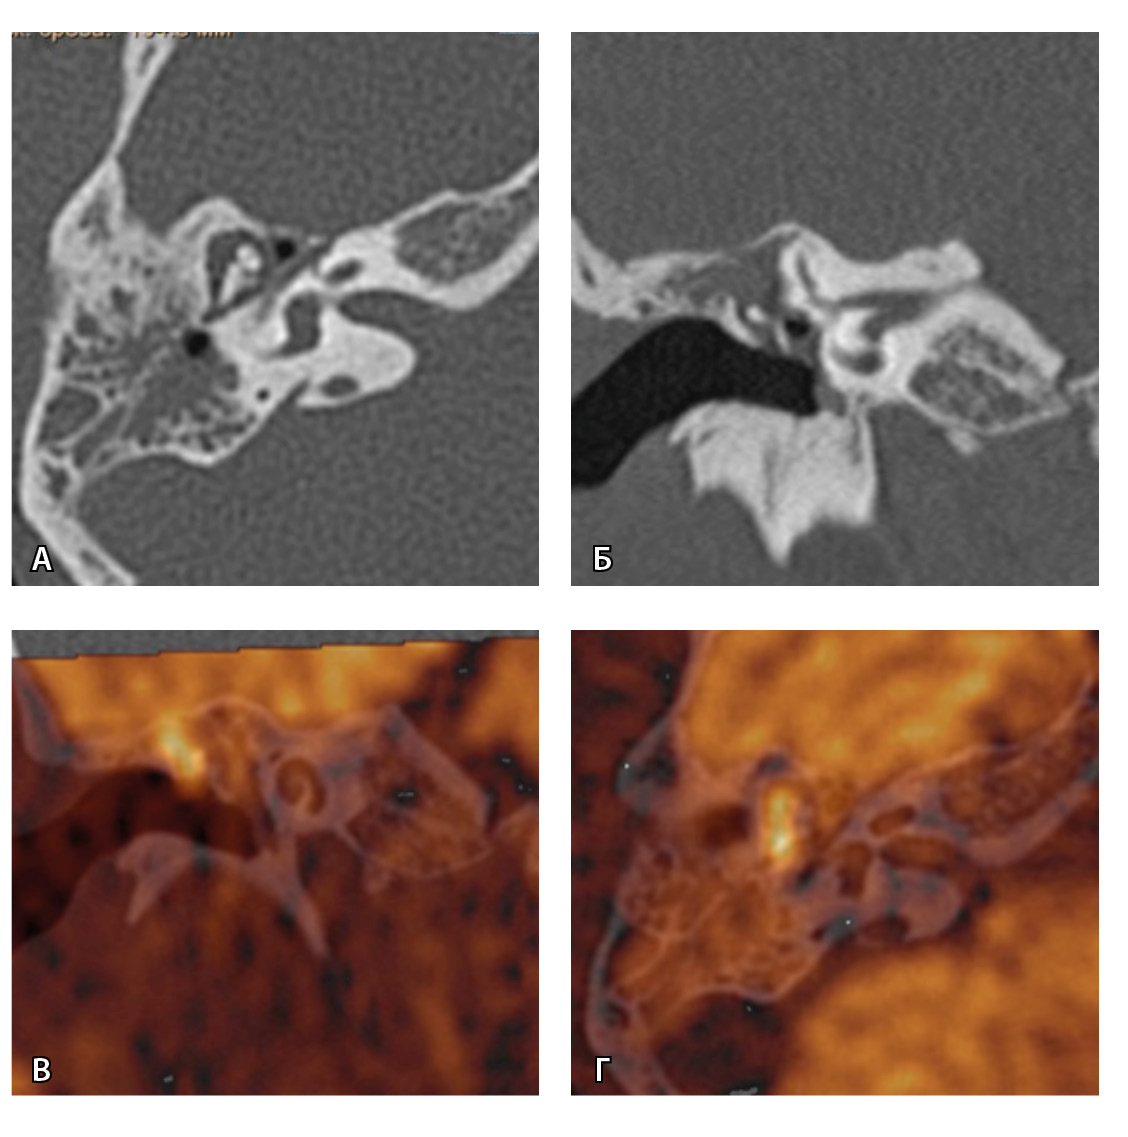

Одним из интересных встреченных нами случаев ложноположительных МР-результатов было грибковое поражение послеоперационной полости с отрицательной динамикой в течение 16 месяцев (рис. 5).

Рис. 5. При первичном послеоперационном исследовании на Т2-взвешенных изображениях во фронтальной плоскости определяется пневматизированная послеоперационная полость (А), без признаков ограничения магнитно-резонансной диффузии (Б). При контрольном исследовании – отрицательная динамика с появлением пристеночных разрастаний вдоль стенок послеоперационной полости (В), ограничивающих магнитно-резонансную диффузию (Г). Данные интерпретированы как рецидив холестеатомы. При оперативном лечении и последующей гистологии – грибковое поражение среднего уха